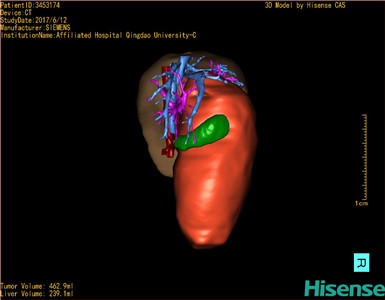

将0.625mm双源薄层CT资料的静脉期和动脉期Dicom格式文件导入海信CAS系统。

通过调节窗宽窗位调整CT序号,对肝实质,胆囊,下腔静脉,肿瘤,肝动脉、门静脉及肝静脉等进行三维重建;系统自动计算肝脏体积。

模拟手术操作,自动计算切除肿瘤体积。肝脏体积为310.9ml,肿瘤体积为437.7ml,肿瘤体积是肝体积的1.4倍,通过比对9-12月正常肝脏体积为321.13±118.91ml,通过术前模拟手术,精准判断切除后剩余肝脏体积能耐受,避免肝衰竭发生。

术前三维重建:

重建图片